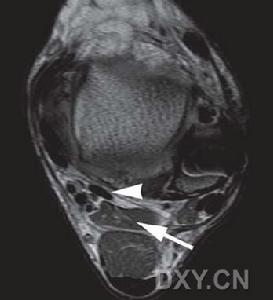

系手外側肌群的1塊肌肉。此肌位於手掌魚際外側皮下,拇短屈肌的外側,遮蓋拇指對掌肌和拇短屈肌的一部分,為長三角形的扁肌。起於腕橫韌帶遠端的橈側半、大多角骨...

簡介 相關詞條拇長展肌,起自橈骨、尺骨的背面和前臂骨間膜,走行於橈側腕伸肌、指伸肌的深面和拇短伸肌的上方,在伸肌支持帶深層,拇長展肌與拇短伸肌腱走行於同一個纖維鞘中,...